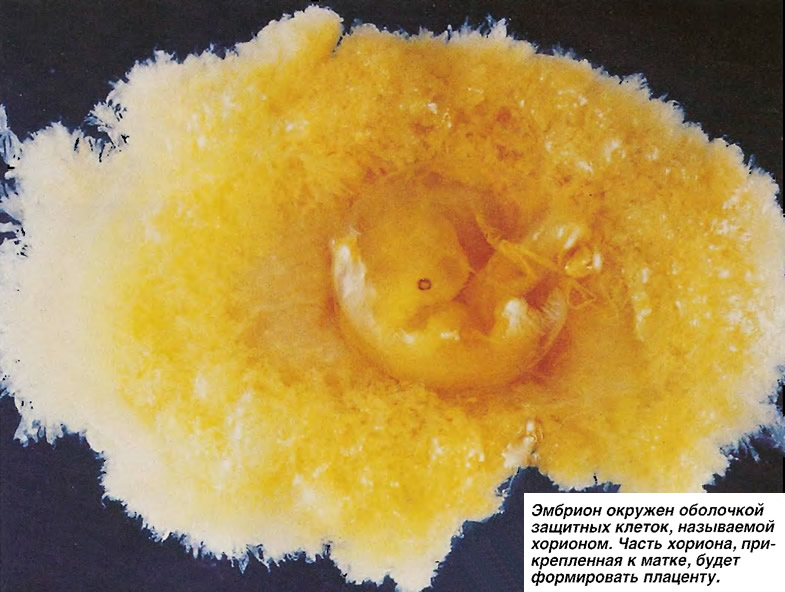

Развитие эмбриона: Что происходит на 3 неделе беременности

Раздел: Фотопанорама